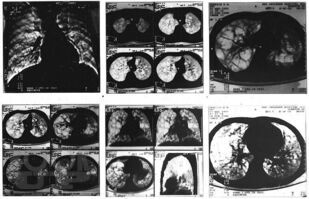

Монография посвящена актуальной теме интерстициальных болезней легких в детском возрасте, многие из которых являются редкими болезнями с тяжелым течением и неблагоприятным прогнозом. В связи с этим своевременная диагности ка и терапия этих болезней необходимы для предотвращения ранней инвалидизации и предотвращения смертности пациентов. Особое внимание уделено гиперсенситивному пневмониту, который в последние годы встречается в педиатрической практике чаще других. В монографии нашли отражение интерстициальные поражения легких при наследственной патологии, диффузных заболеваниях соединительной ткани, системных васкулитах, лекарственных поражениях, болезнях накопления, легочных геморрагиях. Обсуждаются также подходы к проблеме ИБЛ у детей раннего возраста.

В книге обобщены современные данные литературы о различных клинических вариантах ИБЛ, со многими из которых авторам непосредственно пришлось иметь дело в практической деятельности на протяжении не одного десятка лет, и, которые представляют наибольший интерес и важность с точки зрения встречаемости и клинической значимости в детском возрасте.